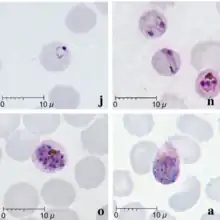

| Giemsa-stained smears of Plasmodium knowlesi infecting human red blood cells | |

Malaria is traditionally diagnosed by examining Giemsa-stained blood films under a microscope; however, differentiating P. knowlesi from other Plasmodium species in this way is challenging due to their similar appearance.[11] P. knowlesi ring-stage parasites stained with Giemsa resemble P. falciparum ring stages, appearing as a circle with one or two dark dots of chromatin.[17] Older trophozoites appear more dispersed, forming a rectangular-shape spread across the host cell called a "band-form" that resembles the similar stage in P. malariae.[17] During this stage, dots sometimes appear across the host red blood cell, called "Sinton and Mulligans' stippling".[17] Schizonts appear, similarly to other Plasmodium species, as clusters of purple merozoites surrounding a central dark-colored pigment.[17]